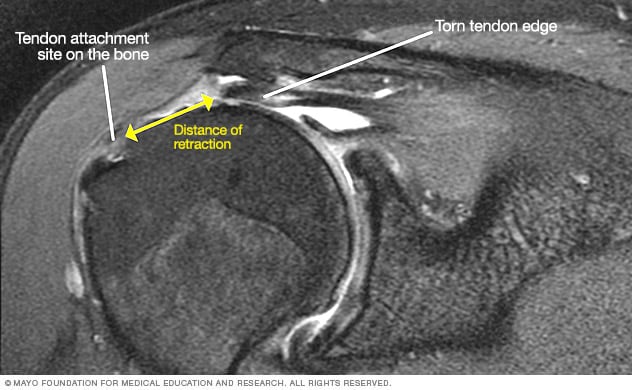

• A diagram of a rotator cuff tear.

• A close-up of a mri.